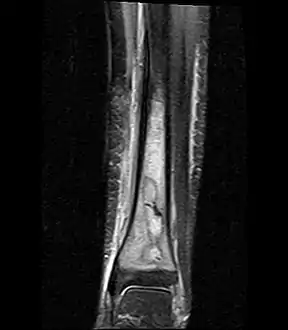

Coronal fat suppressed STIR image showing, bone marrow and subcutaneous edema as well as subperiosteal edema. The thin hypointense rim surrounding the intramedullary collection represents the reactive interface between the abscess and the body's attempt to wall it off.